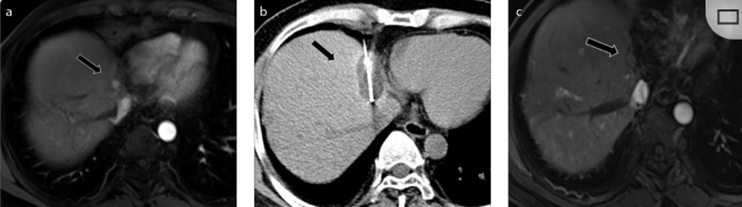

(a)轴向CT显示病变位置毗邻心脏和上腔静脉(黑色箭头)。1个月后的轴向(e)和冠状位(f)增强CT扫描显示低密度区域,由于肉芽组织反应引起的边缘增强。